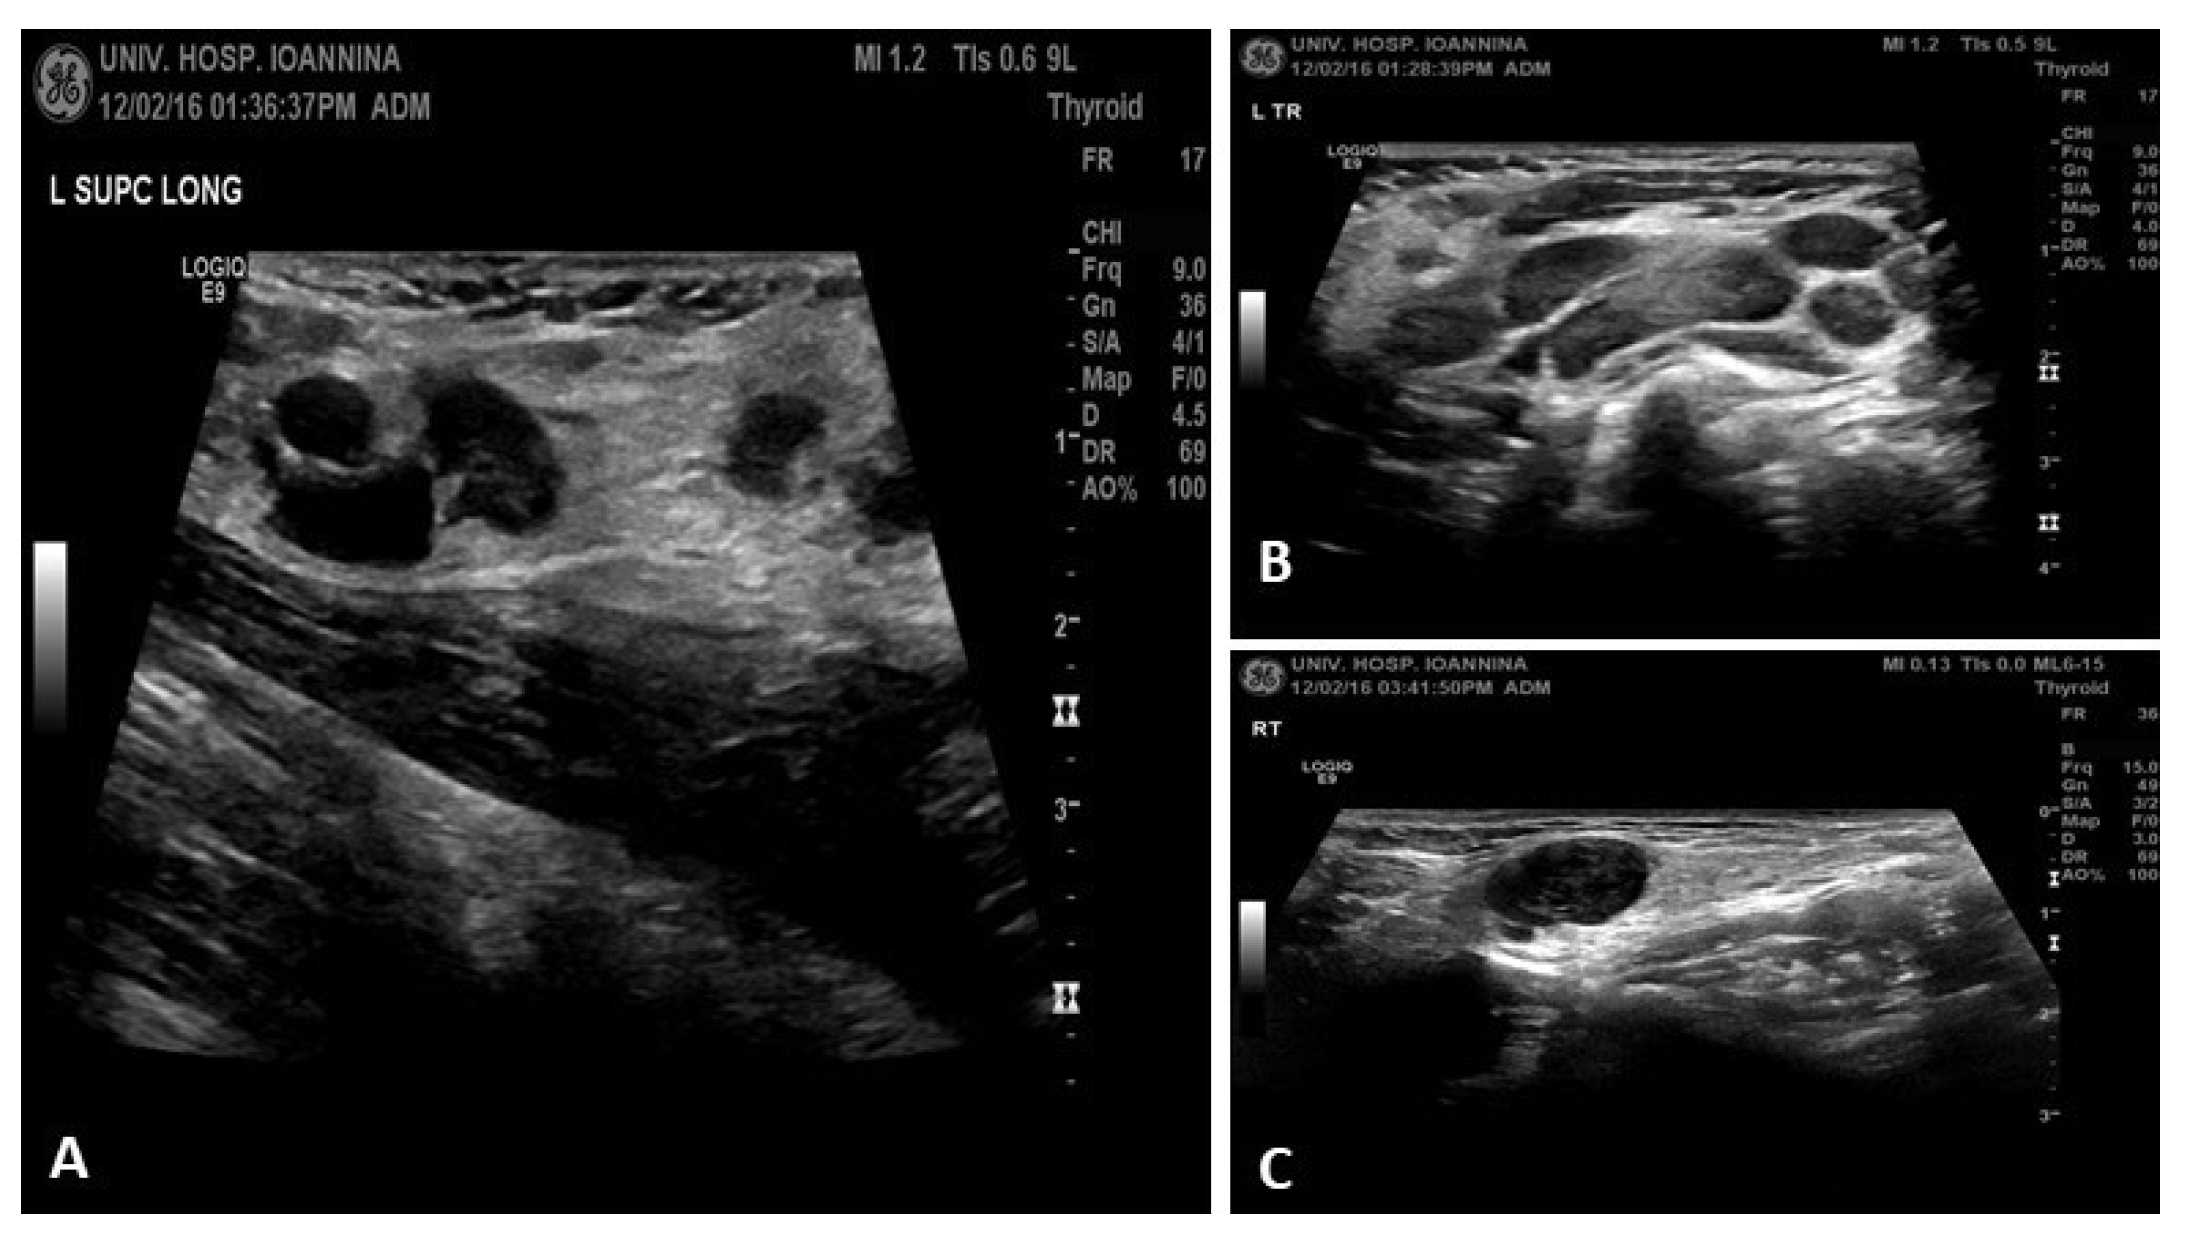

Ultrasound: revealed multiple swollen hypoechoic and rounded lymph nodes in cervical and supraclavicular region (Figure 2).

Figure 2. Ultrasound findings (A) In the supraclavicular regions, multiple enlarged lymph nodes are also revealed that locally converge. Some of them appear hypoechoic and rounded, the largest is on the left with a maximum diameter of ~1.3 cm. (B, C) In the cervical regions and within the parotid glands, more commonly on the left, multiple enlarged lymph nodes of maximum diameter up to 2cm are observed, which in places converge with an oval morphology and normal architecture.

In the follow-up one month later, she was asymptomatic (Figure 5 A), with good appetite and weigh gain, with no palpable cervical and supraclavicular lymph nodes and ultrasound almost normal (Figure 5 B), and leucopenia was recovered, lymphopenia remained for some months. She was advised to have regular check-ups initially every month & three months, immunological check-up every 6-12 months or in case of reappearance of symptoms.

Figure 5. (A) Patient in follow-up, without lymphadenopathy; (B) Ultrasound: 2 small lymph nodes with normal architecture and echo structure.